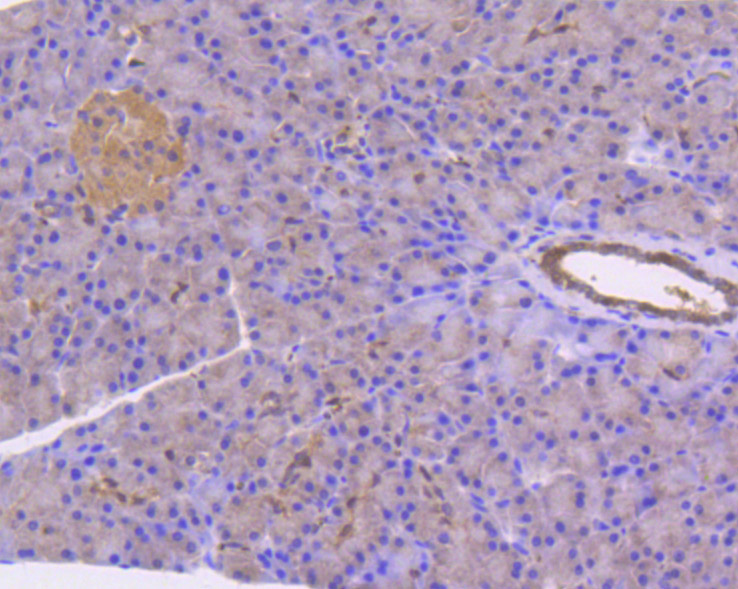

Immunohistochemical analysis of paraffin-embedded mouse pancreas tissue using anti-STAT3 antibody. The section was pre-treated using heat mediated antigen retrieval with Tris-EDTA buffer (pH 8.0-8.4) for 20 minutes.The tissues were blocked in 5% BSA for 30 minutes at room temperature, washed with ddH2O and PBS, and then probed with the primary antibody (HA750120, 1/50) for 30 minutes at room temperature. The detection was performed using an HRP conjugated compact polymer system. DAB was used as the chromogen. Tissues were counterstained with hematoxylin and mounted with DPX.